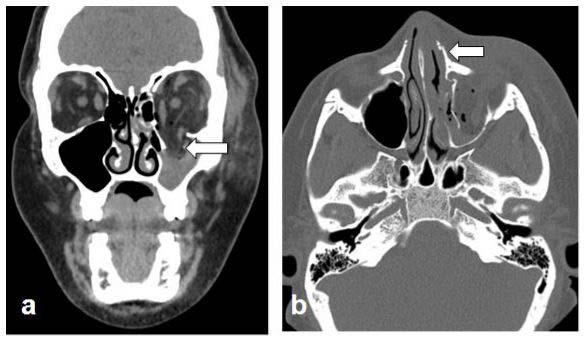

By recognizing high imaging utilization, location and imaging patterns specific to IPV, old injuries of different body parts, and injuries inconsistent to provided history, radiologists can identify victims of IPV even when the victims are not forthcoming.